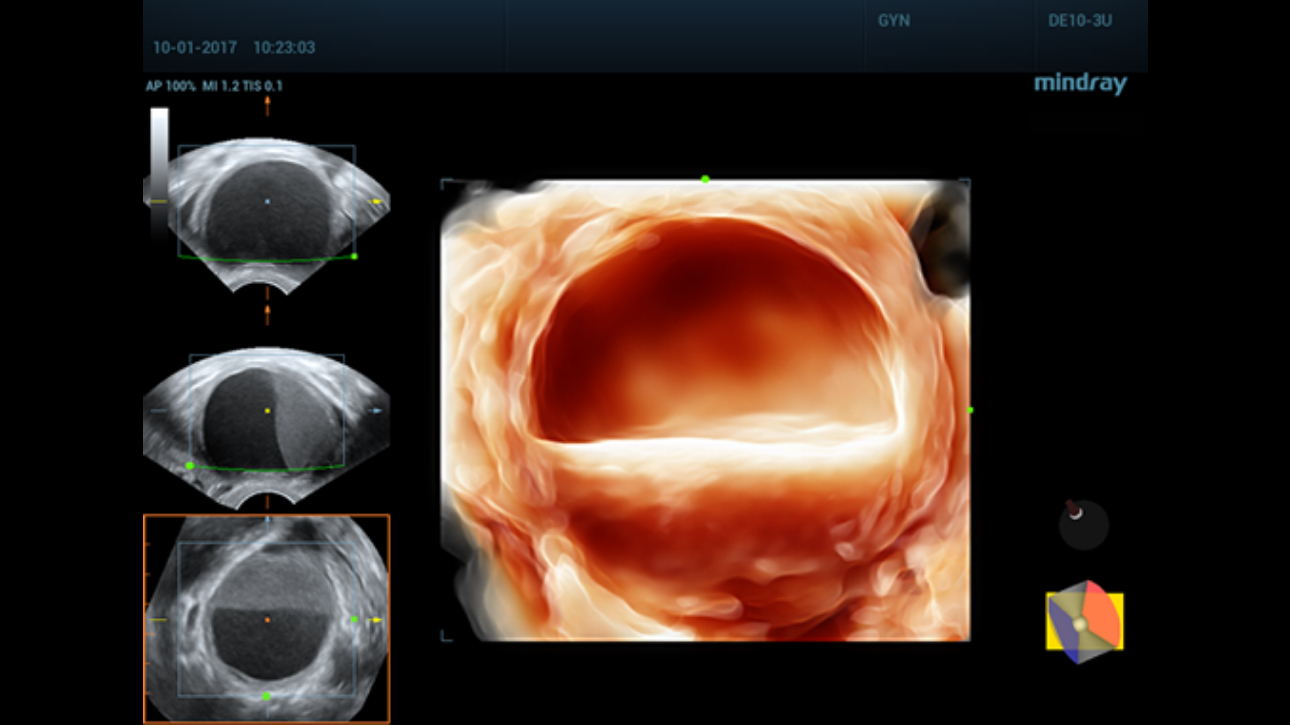

A simple and well-tolerated ultrasound procedure used to assess the patency of the fallopian tubes, as well as detect abnormalities of the uterus and endometrium.

Comprehensive upgrading on iLive to significantly improve the detailed resolution as well as anatomical realism. Hyaline is a new rendering method that dynamically applies transparency to rendered structures for a more comprehensive view of anatomy, therefore better displaying internal anatomy from a solid surface.